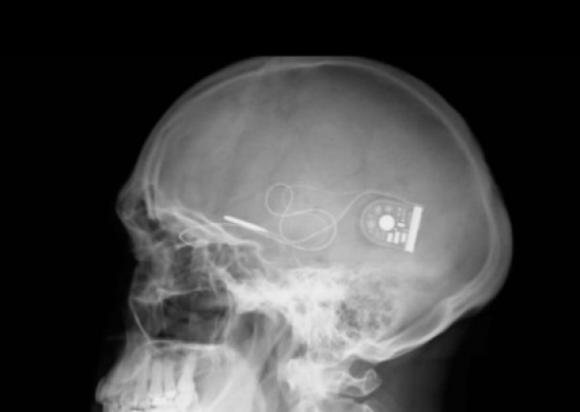

El chip se coloca detrás de la retina, desde donde un cable fino llega hasta una unidad de control bajo la piel detrás del oído, permitiendo que los pacientes perciban luz y distingan formas.

Durante la cirugía se instaló el chip detrás de la retina, desde donde un cable fino llega hasta una unidad de control bajo la piel detrás del oído, permitiendo que los pacientes perciban luz y distingan formas.

Cuando la luz entra por el ojo y alcanza el chip, ésta estimula a los pixeles que envían una señal electrónica al nervio óptico, y éste al cerebro. La sensibilidad del chip puede ser alterada a través de un disco magnético localizado en el cuero cabelludo.